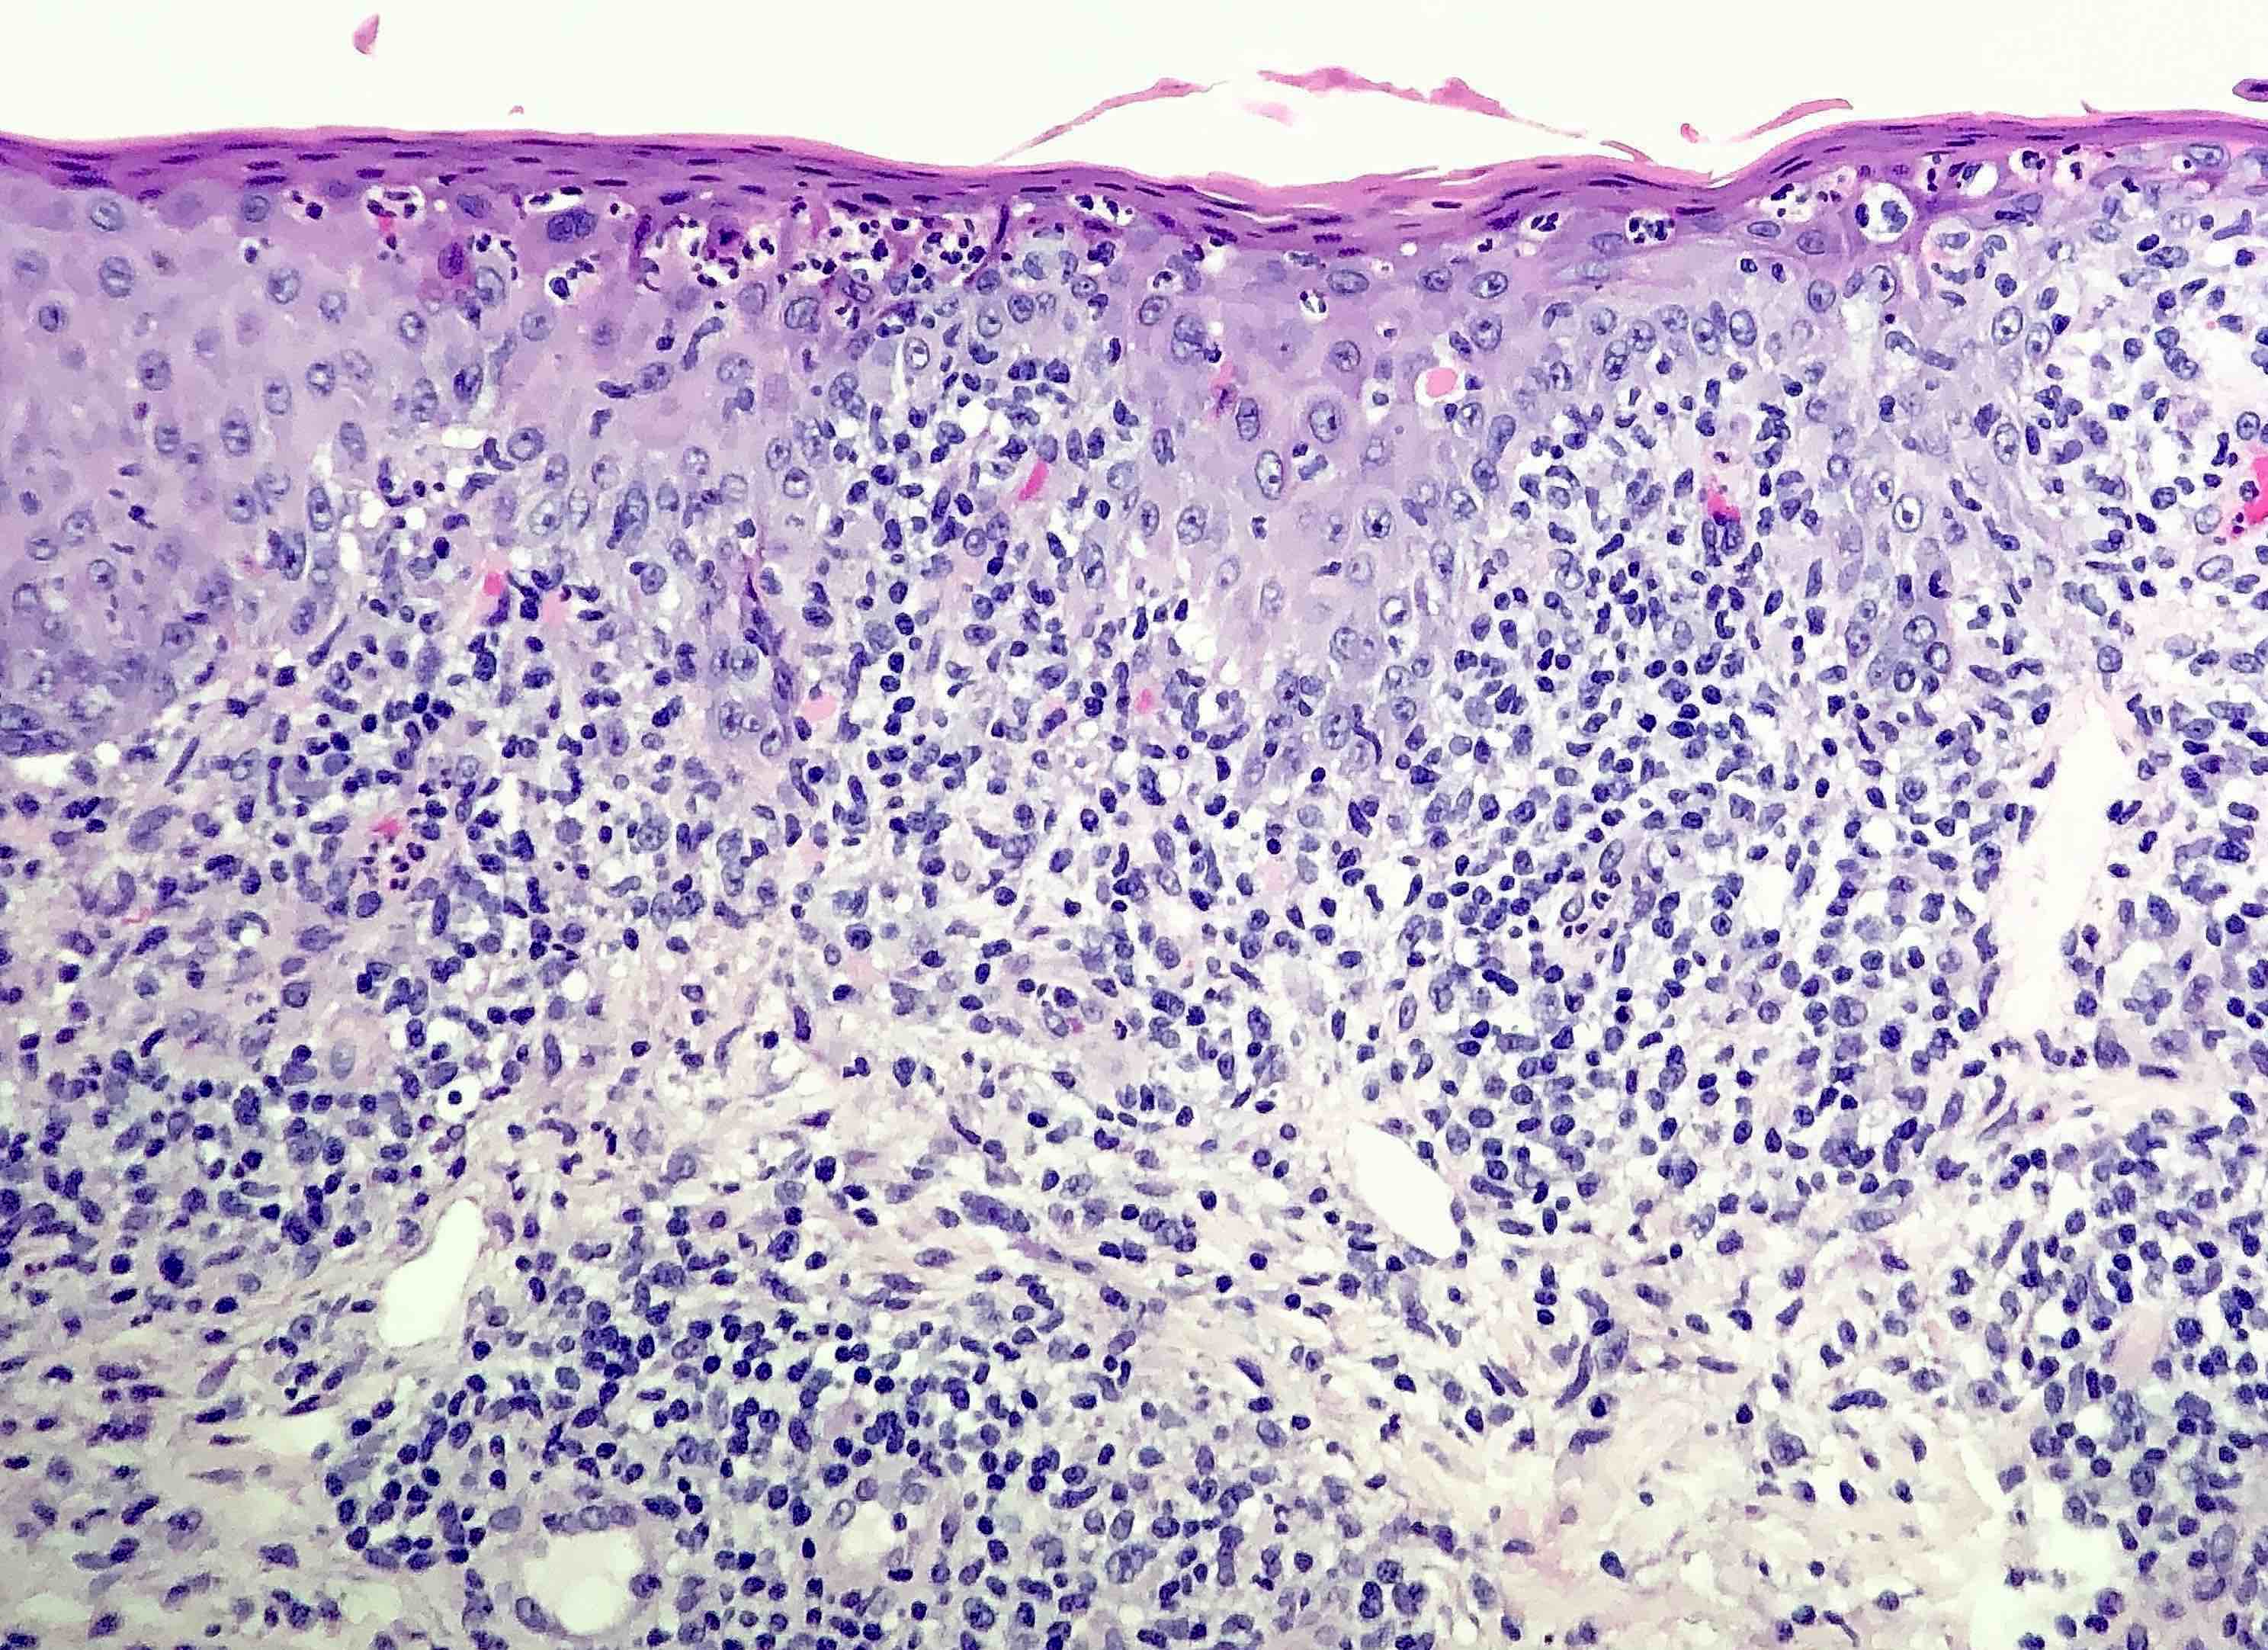

- Secondary syphilis:

- Lichenoid superficial and deep perivascular and periadnexal lymphohistiocytic inflammation with admixed plasma cells

- Plasma cells may be absent in 33% of biopsies

- Eosinophils can be present

- Marked endothelial swelling and proliferation of blood vessels can be seen

- Commonly identified are vacuolar interface change, acanthosis or lymphocyte exocytosis

- Psoriasiform lymphohistiocytic inflammation with plasma cells (see comment)

- Comment: There is psoriasiform epidermal hyperplasia with superficial and deep perivascular lymphohistiocytic infiltrate. Admixed plasma cells are also noted. The infiltrate forms a band beneath the hyperplastic epidermis and envelopes some of the adnexal structures. Endothelial swelling of the superficial vascular plexus is present. A treponemal immunohistochemical stain shows numerous coiled spirochetes in the lower half of the epidermis. These findings are diagnostic of syphilis.